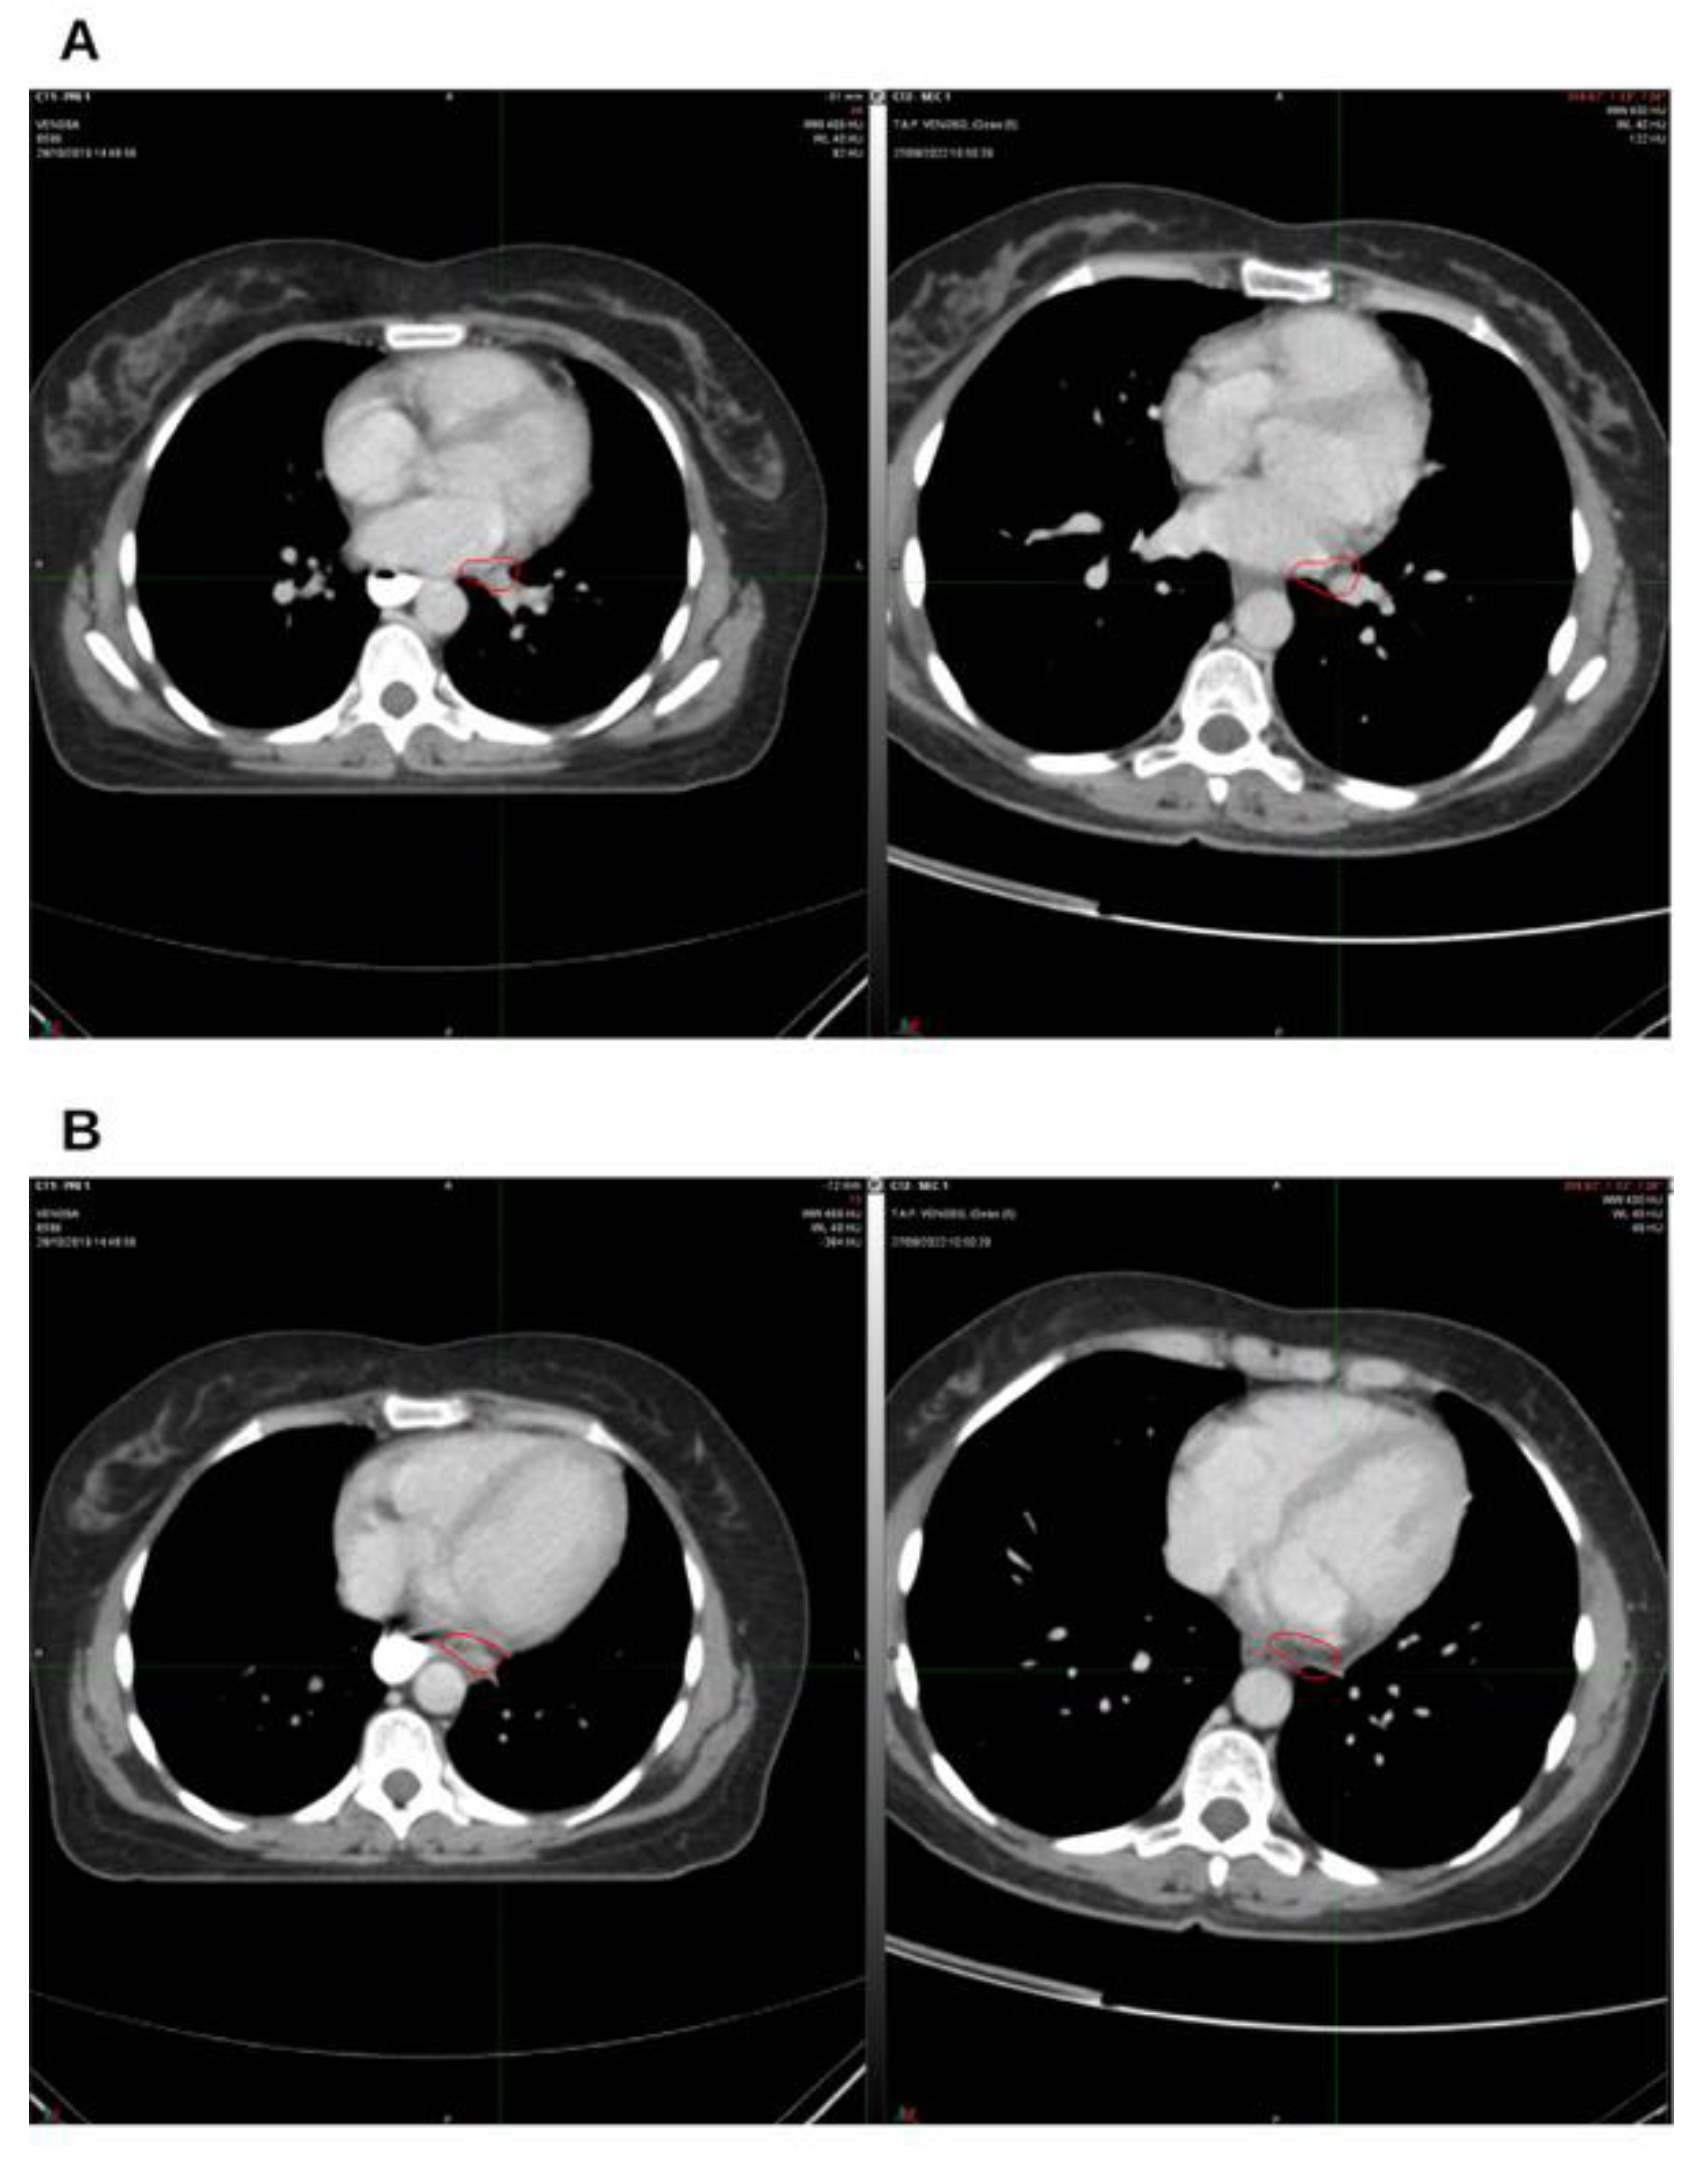

Background and Clinical Significance: Breast cancer is the most frequent malignancy in women. Advanced metastatic breast cancer is considered a treatable but incurable condition, with a median overall survival of only 2-3 years. Among its subtypes, triple-negative breast cancer (TNBC) accounts for a high proportion of breast cancer–related deaths. It is characterized by an aggressive clinical course, early recurrence, and a strong propensity for visceral and brain metastases. Case Presentation :We report the case of a Caucasian woman who, two years after being initially diagnosed and treated for TNBC, developed disease relapse with lung and mediastinal lymph node metastases. The patient received three months of chemotherapy combined with an adjuvant integrative protocol consisting of melatonin, cannabidiol, and oxygen–ozone therapy. This combined approach led to the complete disappearance of the lung nodules. Subsequently, stereotactic radiotherapy was performed and, in association with the ongoing integrative treatment, resulted in a significant reduction of mediastinal adenopathy. Introduction of immunotherapy, supported continuously by the same adjuvant strategy, achieved a complete and durable remission. Strikingly, the patient remained disease-free five years after the diagnosis of lung and mediastinal metastases. Conclusions: This clinical case highlights the potential benefit of using melatonin, cannabidiol, and oxygen–ozone therapy as part of an integrative approach in patients with aggressive metastatic TNBC. While it is not possible to establish causality from a single case, the sustained remission observed suggests that such unconventional adjuvant strategies could play a supportive role in enhancing the efficacy of standard oncologic therapies.